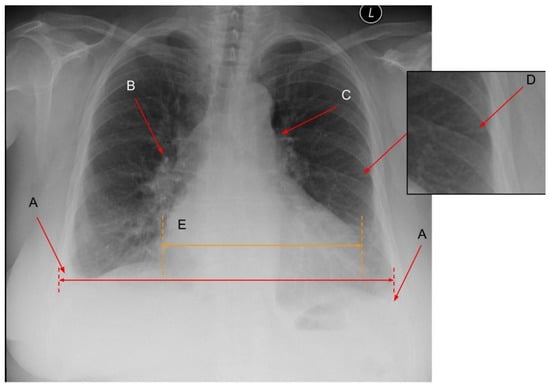

2. Chest X-ray

2.1. Pulmonary Features of HF in CXR

2.2. Cardiac Abnormalities Related to HF in CXR

- Knudsen, C.W.; Omland, T.; Clopton, P. Diagnostic Value of B-Type Natriuretic Peptide and Chest Radiographic Findings in Patients with Acute Dyspnea. ACC Curr. J. Rev. 2004, 13, 47–48. [Google Scholar] [CrossRef]

- Fonseca, C.; Mota, T.; Morais, H.; Matias, F.; Costa, C.; Oliveira, A.G.; Ceia, F.; EPICA Investigators. The Value of the Electrocardiogram and Chest X-ray for Confirming or Refuting a Suspected Diagnosis of Heart Failure in the Community. Eur. J. Heart Fail. 2004, 6, 807–812, 821–822. [Google Scholar] [CrossRef]

- McKee, J.L.; Ferrier, K. Is Cardiomegaly on Chest Radiograph Representative of True Cardiomegaly: A Cross-Sectional Observational Study Comparing Cardiac Size on Chest Radiograph to That on Echocardiography. N. Z. Med. J. 2017, 130, 57–63. [Google Scholar]